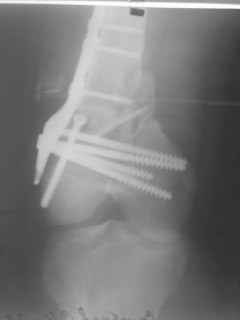

01.12.09г. оперировал больного с подобной травмой в ЦРБ на 4-е сутки после ДТП. Перелом открытый - рана находилась медиально чуть выше надколенника длиной примерно 3-4 см. До этого при поступлении было выполнено ПХО раны и скелетное вытяжение. На момент операции рана без признаков воспаления, состояние больного удовлетворительное.На первичных снимках перелом А3. На операции оказалось С3. Перелом фиксирован мыщелковой пластиной. Для репозиции понадобился медиальный доступ. Медиальный блок дополнен костно-губчатым аутотрансплантатом. На сегодняшний день раны заживают первично, швы еще не сняты, температура тела нормальная, отек бедра значительно уменьшился, имеется анемия средней степени, проводится ЛФК. Фото досылаю

Чем остеосинтез аппаратом в этом конкретном случае был бы предпочтительнее - и менее инвазивно, и пластику бы не надо было делать, и ось можно было бы лучше контролировать, включая послеоперационный период. А сейчас варусный коллапс градусов 15, и для исправления оси потребуется отдельная операция...